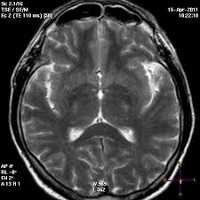

- МРТ (магнитно-резонансная терапия) с внутривенным контрастированием;

- КТ (компьютерная томография) головного мозга;

- На МРТ головного мозга имеются дистрофические нарушения и уменьщение объёма коры больших полушарий.

Всех пострадавших с черепно-мозговой травмой в обязательном порядке транспортируют в стационар, где после подтверждения диагноза устанавливают им постельным режим на срок, который зависит от клинических особенностей течения заболевания. Отсутствие признаков очаговых поражений головного мозга на КТ и МРТ головного мозга, а также состояние пациента, позволяющее воздержаться от активного медикаментозного лечения, позволяют решить вопрос в пользу выписки пациента на амбулаторное лечение.

Методом выбора при диагностике ушиба головного мозга является КТ головного мозга. На КТ определяют ограниченную зону пониженной плотности, возможны переломы костей свода черепа, субарахноидальное кровоизлияние. При ушибе мозга средней степени тяжести на КТ или спиральной КТ в большинстве случаев выявляют очаговые изменения (некомпактно расположенные зоны пониженной плотности с небольшими участками повышенной плотности).

Обязательным методом обследования пострадавших с черепно-мозговой травмой является компьютерная томография. Относительными противопоказаниями к ее проведению могут служить геморрагический или травматический шок, а также нестабильная гемодинамика. С помощью КТ определяют патологический очаг и его расположение, количество и объем гипер- и гиподенсивных зон, положение и степень смещения срединных структур головного мозга, состояние и степень повреждения головного мозга и черепа.

- Томография. Проанализировать степень морфологических изменений можно при помощи МРТ головного мозга. Этот метод также позволяет дифференцировать энцефалопатию от других церебральных заболеваний: болезни Альцгеймера, внутримозговой опухоли, энцефалита, рассеянного энцефаломиелита, инсульта, кортикобазальной дегенерации, болезни Крейтцфельдта — Якоба и пр.